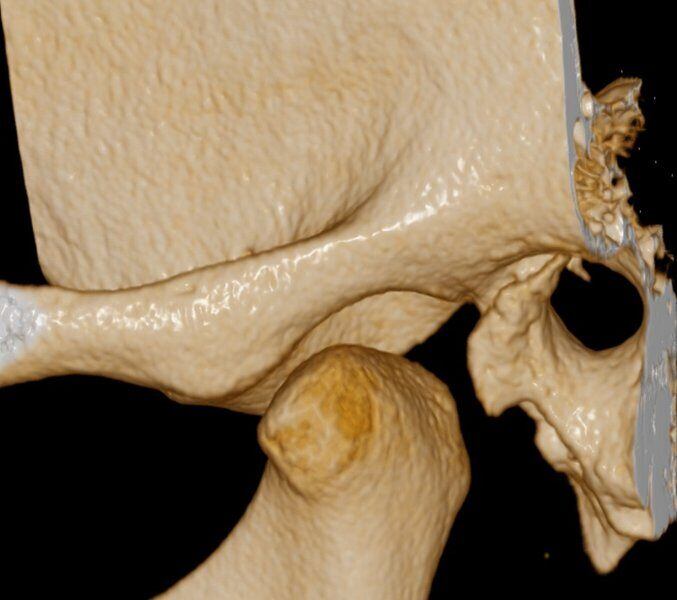

ATM Bocca Chiusa